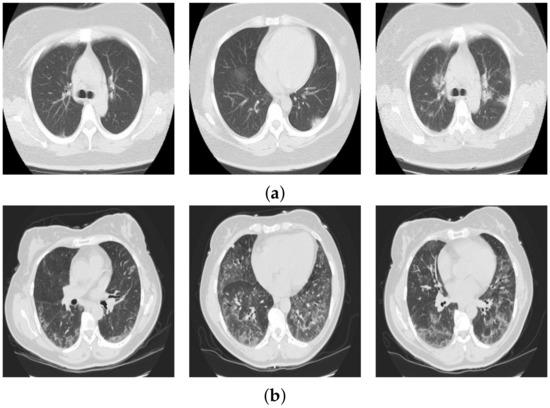

3.1. COVID19-CT Database

3.2. Mosmed Database

3.3. Augmented Datasets